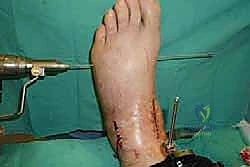

خطوات جراحة تثبيت مفصل الكاحل الأمامي بالتفصيل (Step-by-Step Surgical Procedure)

تُجرى العملية تحت التخدير العام أو النصفي (الشوكي)، وتستغرق عادةً بين ساعتين إلى ثلاث ساعات، وتتطلب دقة ومهارة فائقتين. إليكم الخطوات الجراحية كما ينفذها الأستاذ الدكتور محمد هطيف:

1. الوضعية والشق الجراحي (Positioning and Incision)

يستلقي المريض على ظهره (Supine position). يتم استخدام عاصبة (Tourniquet) حول الفخذ لتقليل النزيف وتوفير رؤية واضحة. يقوم الدكتور هطيف بإجراء شق طولي أمامي فوق مفصل الكاحل، عادة بين وتر العضلة الظنبوبية الأمامية (Tibialis Anterior) ووتر العضلة الباسطة الطويلة لإصبع القدم